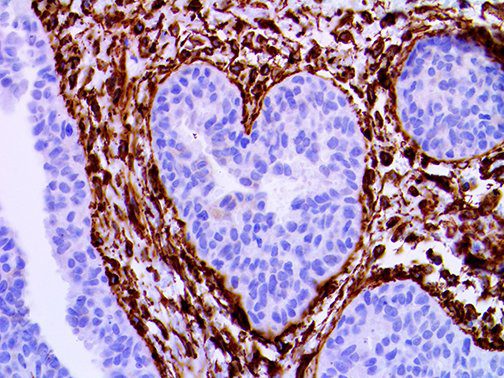

The first cytokines released are interleukin 1β (IL-1β) and tumor necrosis factor-α (TNF-α), which attract a variety of circulating white blood cells (WBCs) to the infection site, including neutrophils, monocytes, macrophages, and natural killer (NK) cells. This response, along with the antipathogenic chemicals released by these cells (i.e., complement), comprise the innate immune response. These cells directly attack the invading pathogen and also release additional cytokines, chief among them interleukin-1 and 6 (IL-6). IL-6 is essential for invoking the adaptive immune response, which calls T-cells, B-cells, and T helper (Th) cells to the infection site. IL-6 also stimulates further recruitment, proliferation and activation of macrophages.

This activation induces inflammatory monocytes to highly express IL-6, starting a localized and then systemic cascade effect that results in hyperproduction of IL-6, which accelerates the inflammatory process. Because IL-6 also increases vascular permeability, excessive levels cause blood vessels to become very leaky. This, along with clotting factors released from vascular endothelial cells, stimulates the coagulation cascade, resulting in microthrombosis (tiny clots), which leads to ischemia and tissue death of the kidney, intestines, heart, liver, brain and extremities.